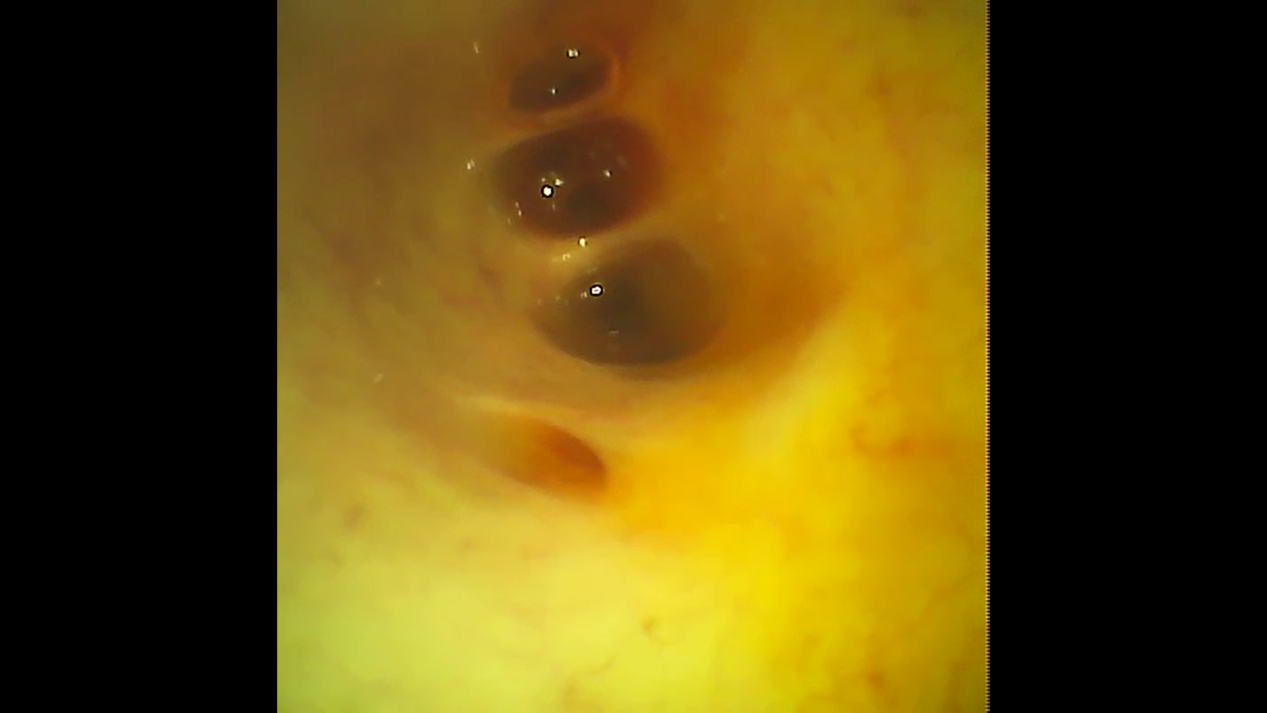

在张涛主任的指导下,征得老大爷和家属的同意后,在医院内镜中心ERCP操作室,由杨文副主任医师进行了我院第一例ERCP下经口电子胆道镜(子母镜)检查。在操作过程中发现,老大爷胆道通畅,胆汁为黄绿色,并未发现阳性结石,距乳头3cm的胆总管下段狭窄,胆总管粘膜稍粗糙,但未见肿瘤。自此,老大爷被明确诊断为胆总管下段狭窄(炎症所致)。经过胆道子母镜的治疗处理,老大爷术后当天晚上及第二天复查血常规、胰腺生化等指标均正常,无腹痛、发热等特殊不适,他悬着的心终于放下了,脸上也露出了久违的笑容。

胆道子母镜图:距乳头3cm胆总管下段狭窄处